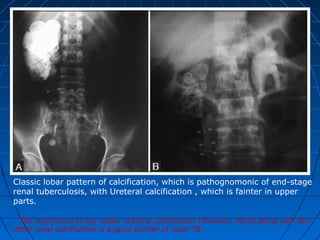

Classic lobar pattern of calcification, which is pathognomonic of end-stage

renal tuberculosis, with Ureteral calcification , which is fainter in upper

parts.

The occurrence of any upper ureteral calcification (however, faint) along with any

other renal calcification is a good pointer of renal TB.